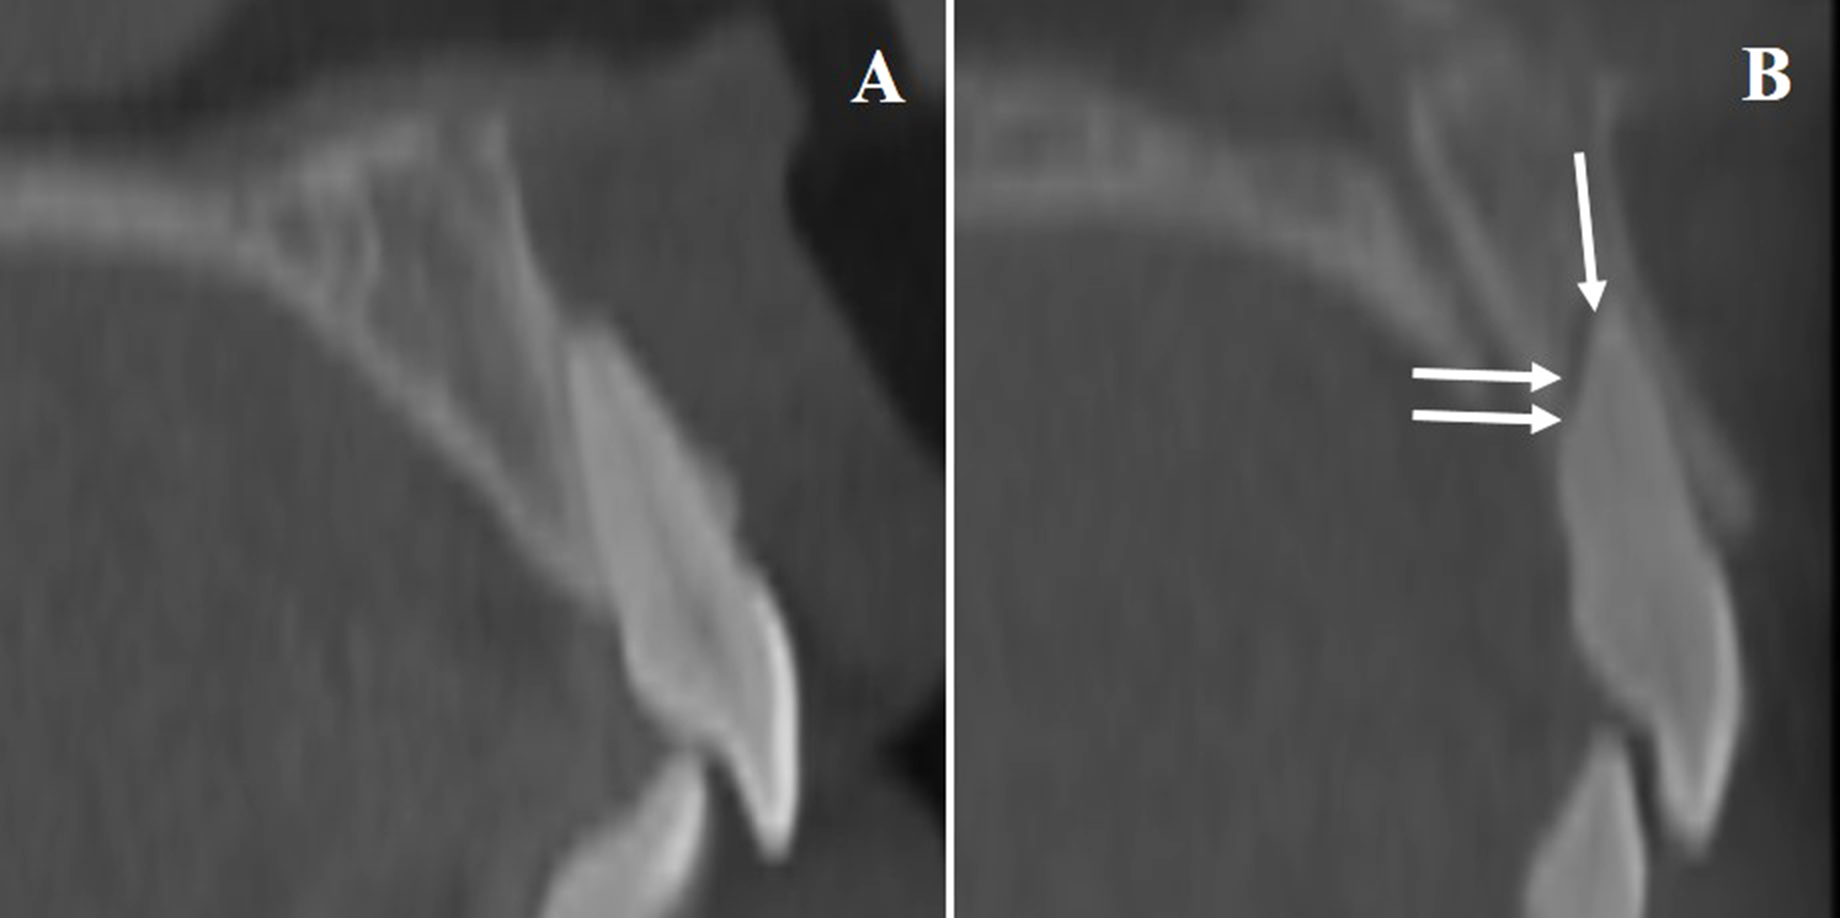

Root resorption was assessed through changes in U1 root length and width, comparing T1 and T2 (Fig. 3). Incisor movement was calculated via CBCT-based cranial base superimposition. Other cephalometric variables recorded included SNA angle, U1-SN angle, and overall treatment duration.

Illustration of Root Resorption in U1. A). Baseline CBCT image of a maxillary central incisor prior to treatment. B). Post-treatment scan revealing evidence of apical and horizontal root resorption (arrows mark the affected zones).